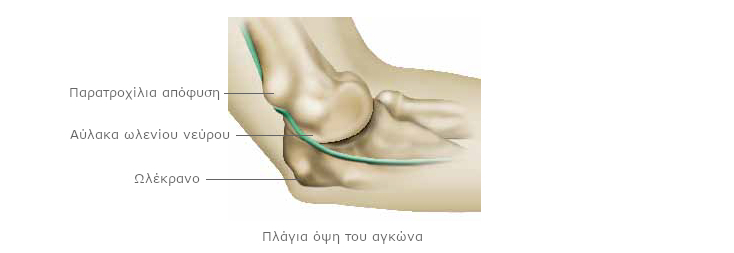

Στην εξωτερική πλευρά του αγκώνα βρίσκεται μέρος του βραχιονίου, που ονομάζεται έξω επικόνδυλος. Στο εσωτερικό, δημιουργείται μια σφαιρική επιφάνεια, που σχηματίζεται από το βραχιόνιο, η παρατροχίλια απόφυση (ή έσω επικόνδυλος).

Ανάμεσα σε αυτά τα δυο, μπορείτε να αισθανθείτε το πίσω μέρος της ωλένης, που ονομάζεται ωλέκρανο. Μεταξύ της παρατροχίλιας απόφυσης και του ωλεκράνου σχηματίζεται μια κοιλότητα, που ονομάζεται αύλακα ωλενίου νεύρου.

Το ωλένιο νεύρο διασχίζει το άνω άκρο. Οι διακλαδώσεις του φτάνουν στο μικρό δάκτυλο και τον παράμεσο του χεριού. Είναι μικτό νεύρο: κινητικό και αισθητικό. Διασχίζει την αύλακα που σχηματίζεται ανάμεσα στην παρατροχίλια απόφυση και το ωλέκρανο. Προστατεύεται και συγκρατείται από έναν ισχυρό σύνδεσμο.